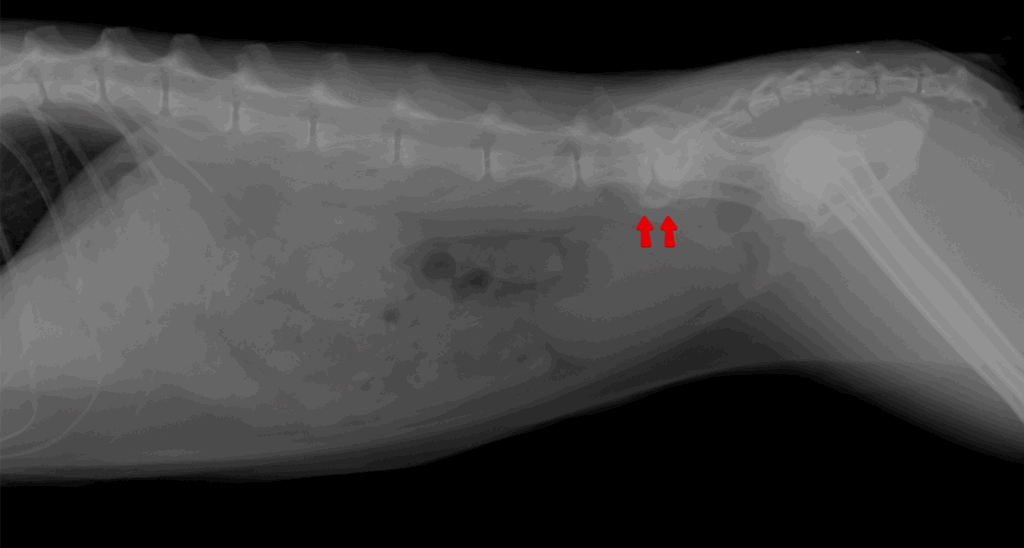

診断するにはレントゲン検査です。

関節にできた骨棘や石灰化病変を確認することで診断していきます。

他にも膝や手首、足首の関節、背骨などにも変形は出ることがあるので、場所を特定するには身体検査も重要になってきます。